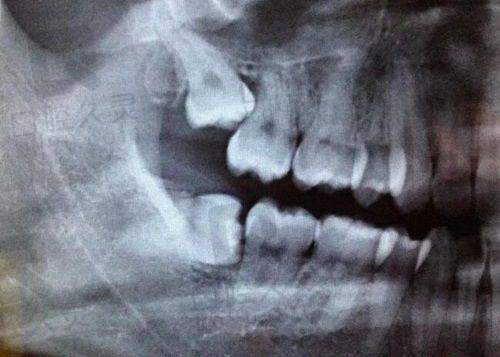

种植牙是将人工种植体植入牙槽骨,待紧密愈合后制作牙冠,能让牙齿更整齐。种出的牙齿就像天生的一样,不会脱落,口腔也没有异物感,特别受患者欢迎。